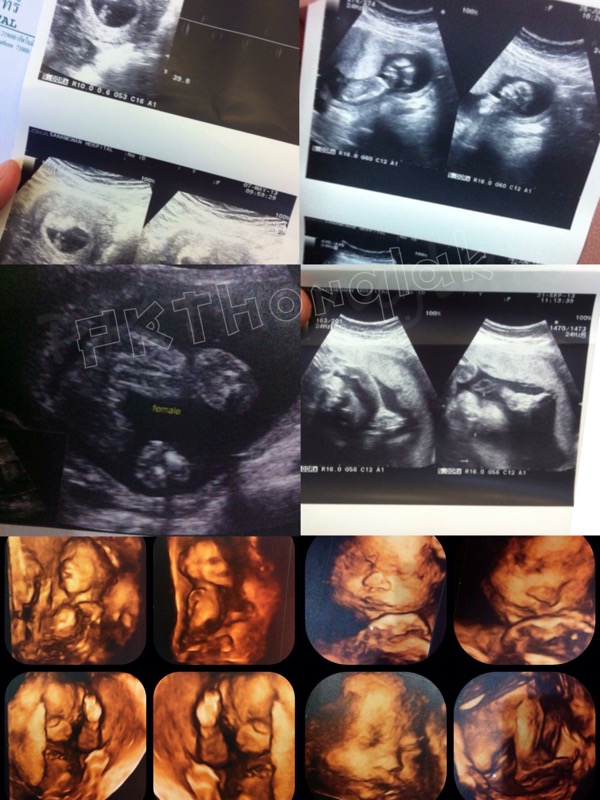

เห่อลูกนะ อยากจะซาวด์ดูเขาทุกๆวันเลย((แต่คุณหมอจะด่าเอา😁) 2D3D4D เราดูหมดอะค่าดูแพงแค่ไหนก็ยอม อันดับแรกอยากรู้ว่าลูกเราคบ32มั้ย😊ผู้

หญิงผู้ชาย🤗🤗